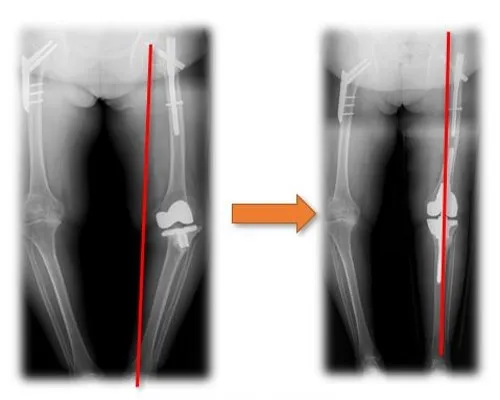

Osteoarthritis Secondary to Hip Dysplasia Treatment

Total Hip Replacement

Through three-dimensional reconstruction of medical CT data, porous implants with bionic trabecular structures such as joint, spine, craniofacial bone and extremities can be manufactured by using three-dimensional printing techniques like electron beam melting, selective laser melting and selective laser sintering. The factors such as porosity, pore size and pore reinforcement can be adjusted for individuals, which is more conducive to bone growth and is better in clinical effect.

Clinical Application 1 Clinical Application 2